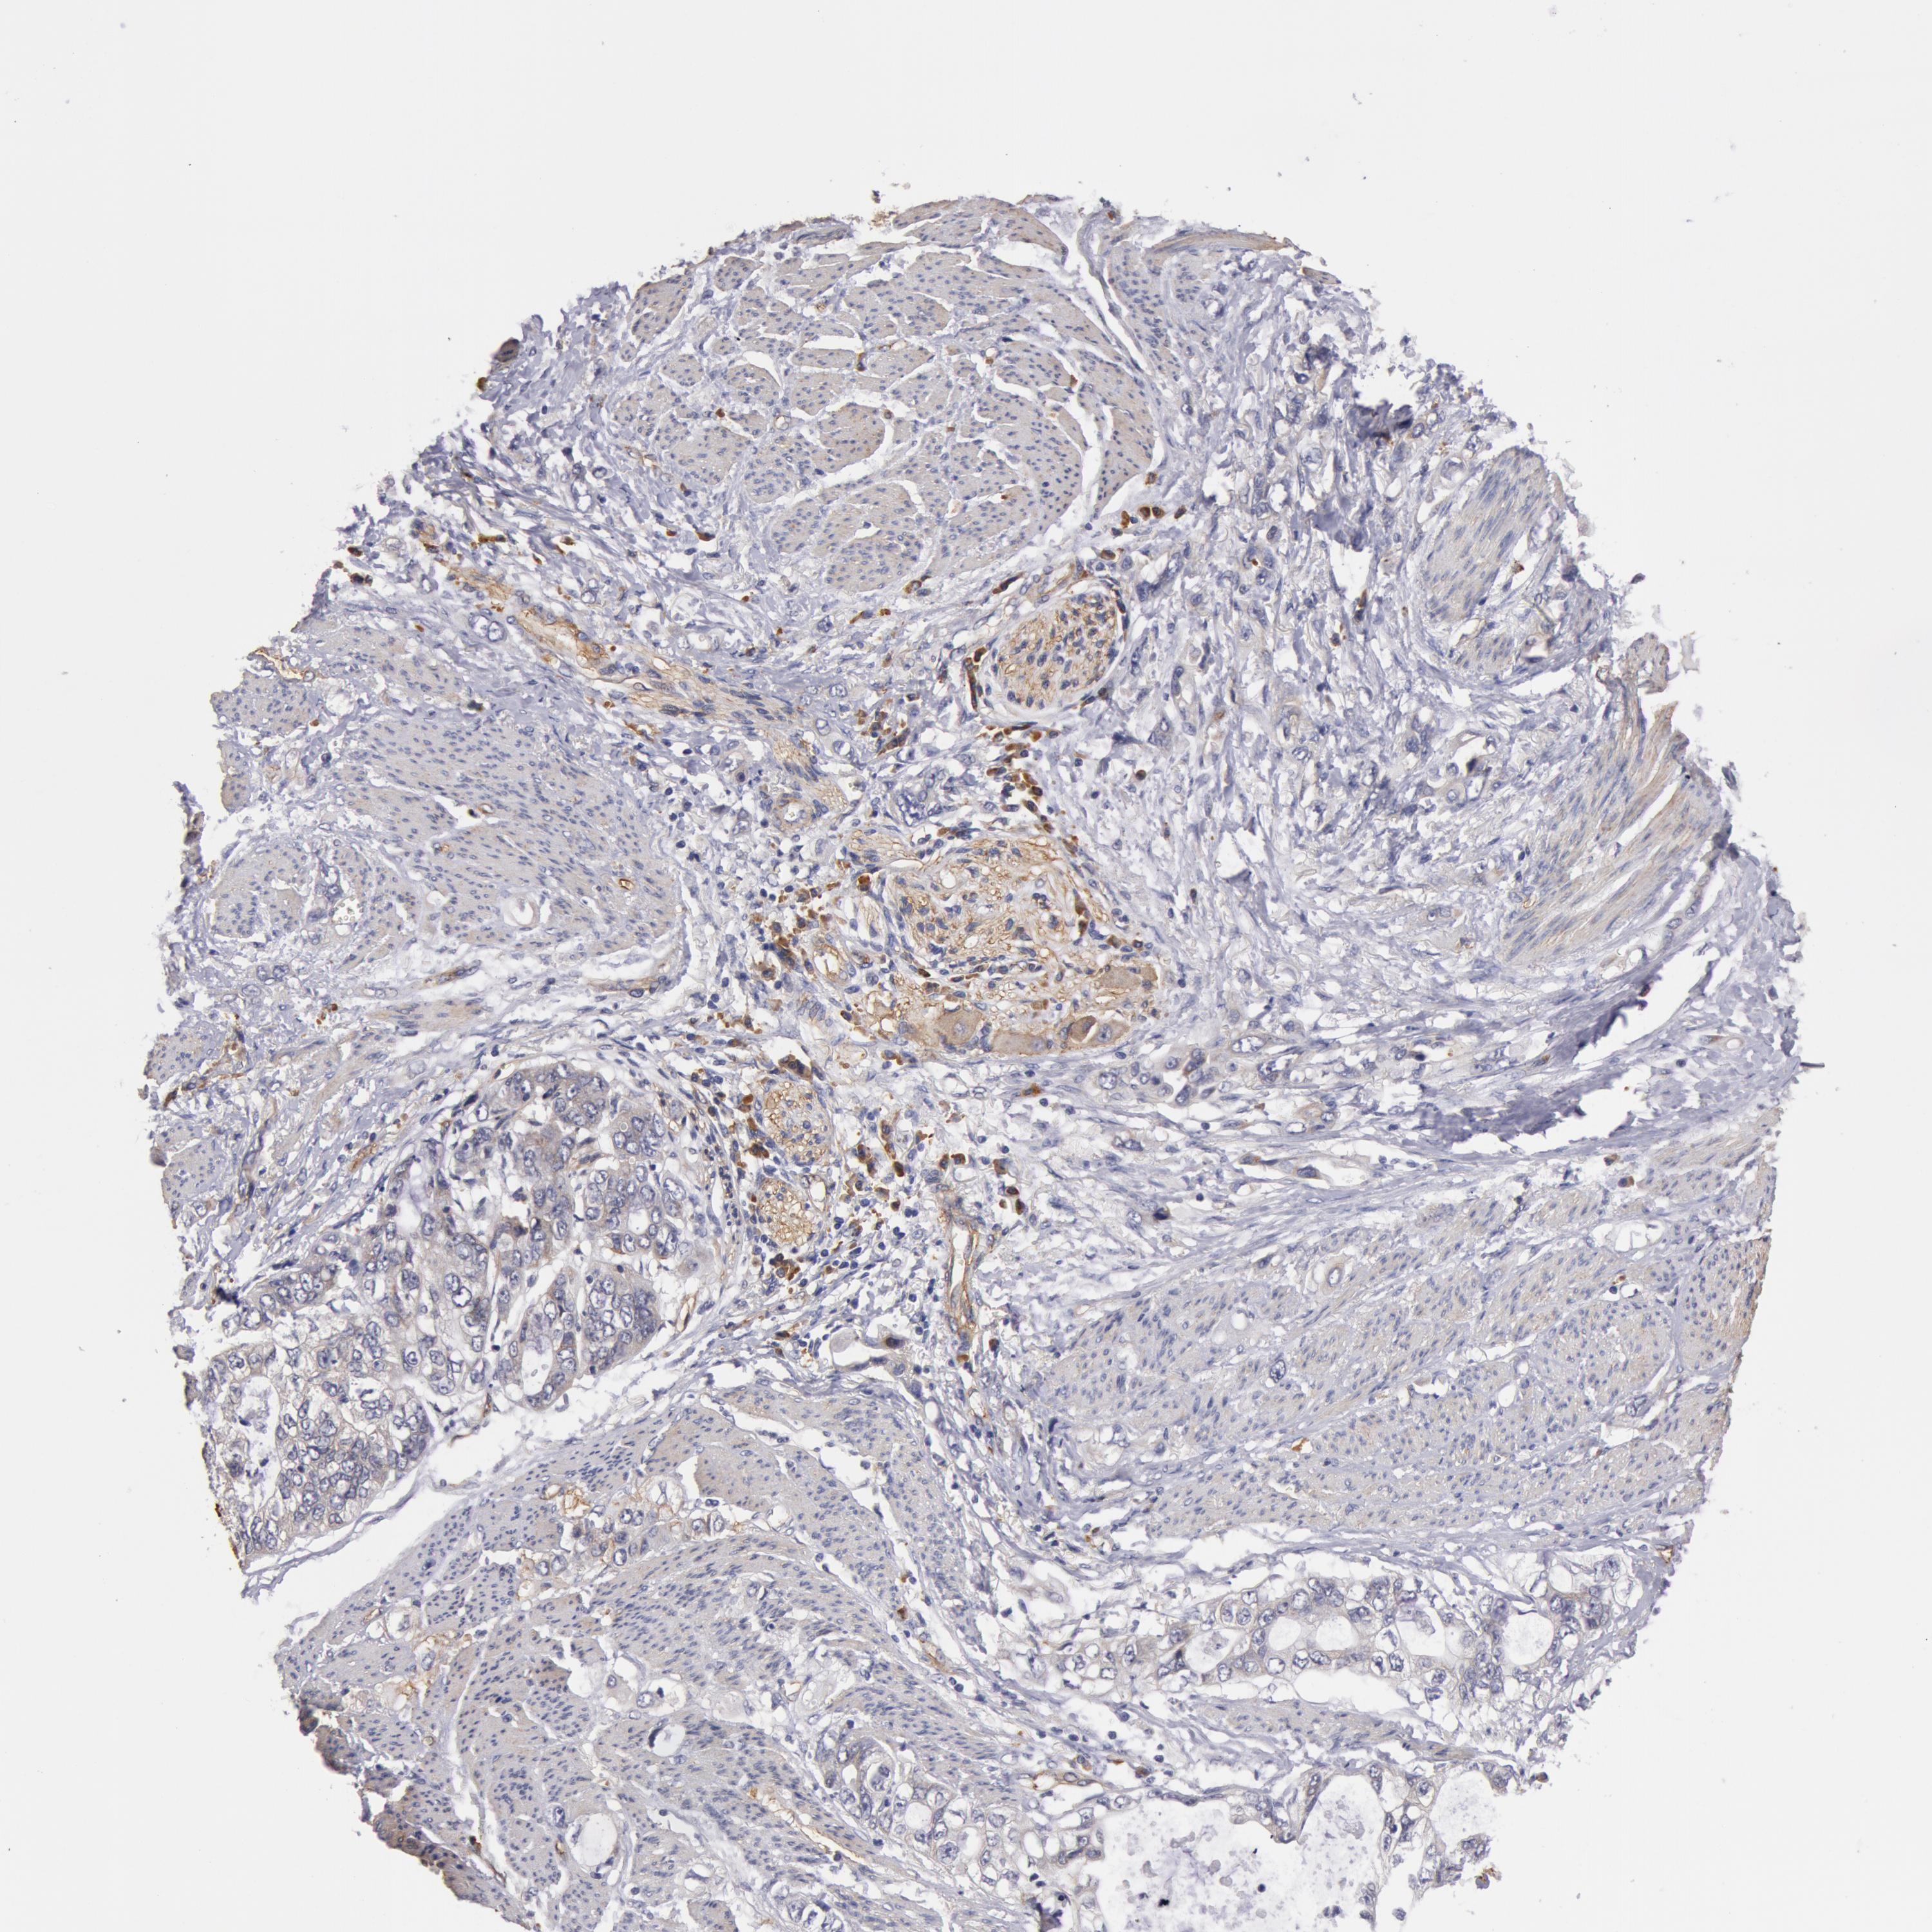

STOMACH CANCER - Protein expressioni

A mouse-over function shows sample information and annotation data. Click on an image to view it in a full screen mode. Samples can be filtered based on level of antibody staining by selecting one or several of the following categories: high, medium, low and not detected. The assay and annotation is described here.

Antibody stainingi

Antibody staining in the annotated cell types in the current human tissue is reported as not detected, low, medium, or high, based on conventional immunohistochemistry profiling in selected tissues. This score is based on the combination of the staining intensity and fraction of stained cells.

Each image is clickable and will lead to virtual microscopy that enables deeper exploration of all samples and also displays staining intensity scores, fraction scores and subcellular localization as well as patient and tissue information for each sample.

Antibody HPA001554

Staining

High

Medium

Low

Not detected

Intensity

Strong

Moderate

Weak

Negative

Quantity

>75%

75%-25%

<25%

None

Location

Nuclear

Cytoplasmic/membranous

Cytoplasmic/membranous,nuclear

Adenocarcinoma, NOS